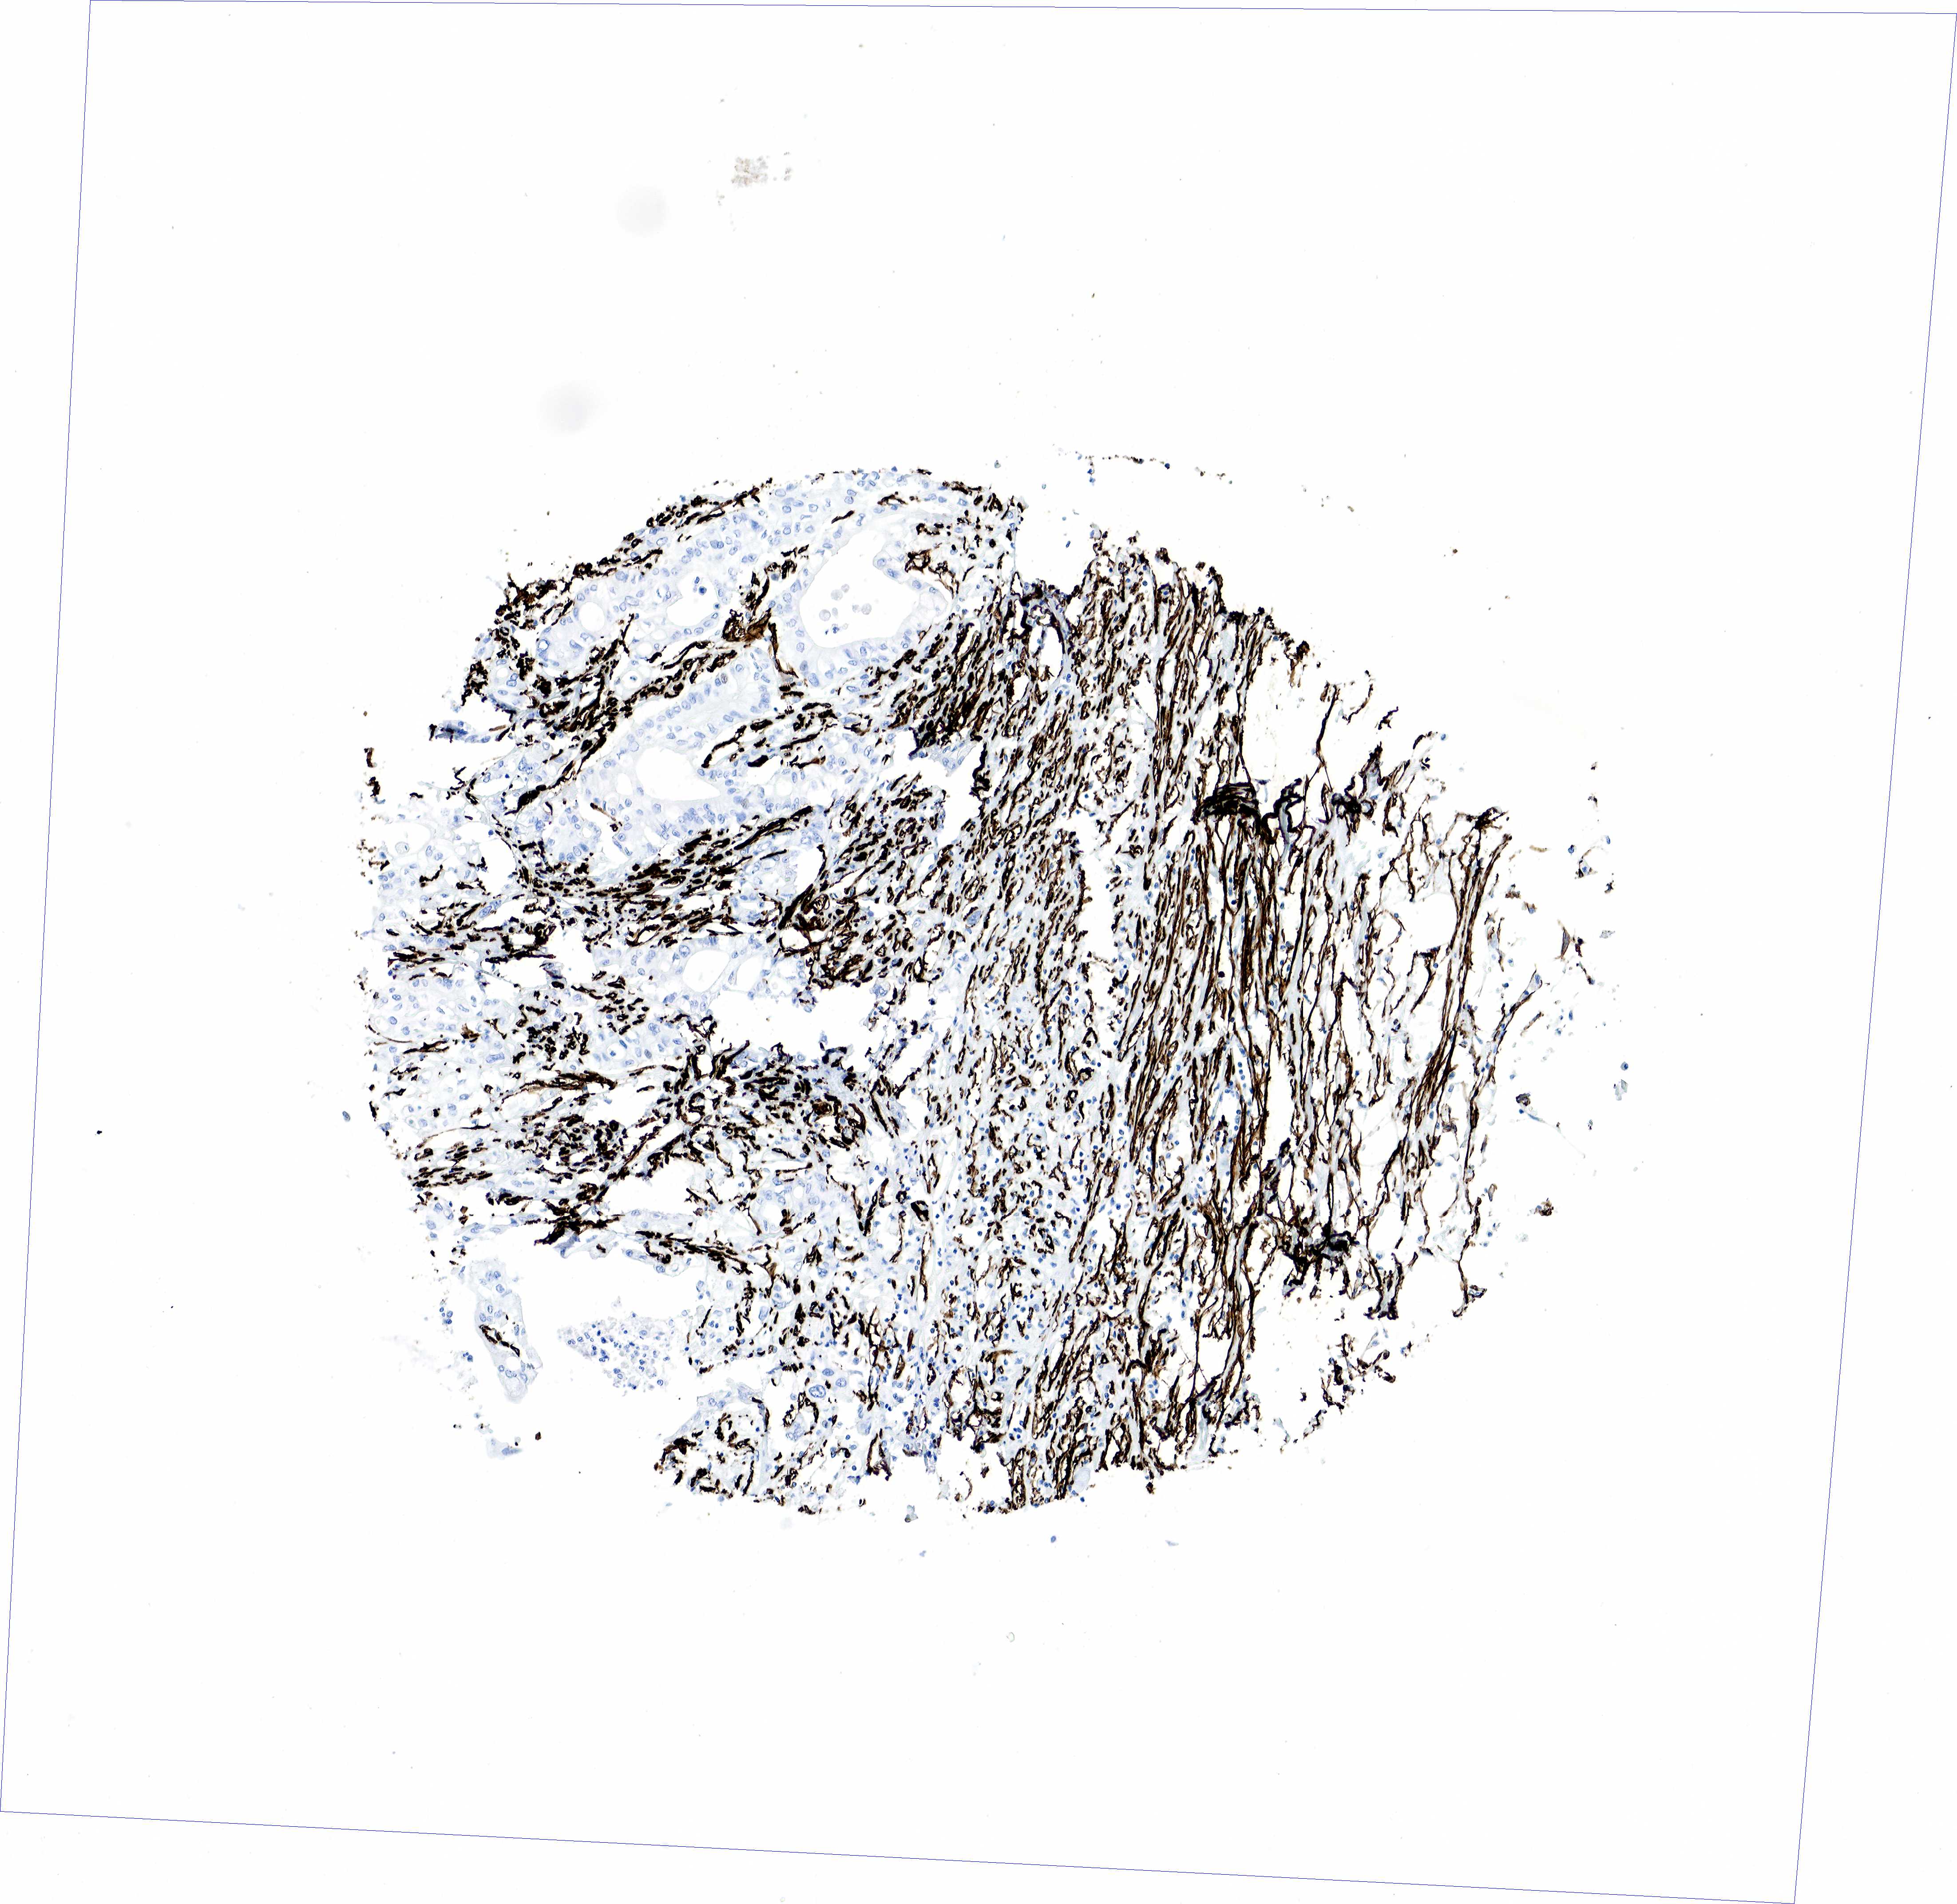

PANCREATIC CANCER - Protein expressioni

A mouse-over function shows sample information and annotation data. Click on an image to view it in a full screen mode. Samples can be filtered based on level of antibody staining by selecting one or several of the following categories: high, medium, low and not detected. The assay and annotation is described here.

Note that samples used for immunohistochemistry by the Human Protein Atlas do not correspond to samples in the TCGA dataset.

Antibody stainingi

Antibody staining in the annotated cell types in the current human tissue is reported as not detected, low, medium, or high, based on conventional immunohistochemistry profiling in selected tissues. This score is based on the combination of the staining intensity and fraction of stained cells.

Each image is clickable and will lead to virtual microscopy that enables deeper exploration of all samples and also displays staining intensity scores, fraction scores and subcellular localization as well as patient and tissue information for each sample.

HPA041264

HPA041271

CAB000002

CAB003761

CAB013531

Adenocarcinoma, NOS